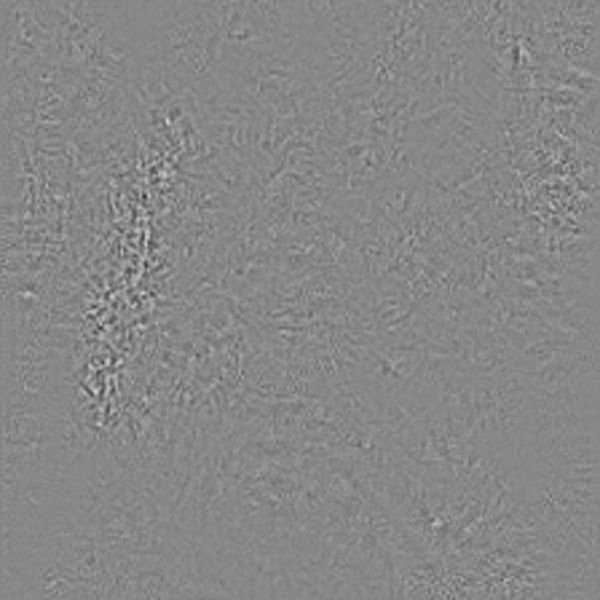

2.3 Guided Grad-CAM

Another backend presented in [7] is Guided Grad-CAM which is a combination of Guided Backpropagation and Grad-CAM in an effort to combine the best of both approaches. When generating attention maps with both backends the resulting attention maps can be combined through simply multiplying them element-wise. The result is a noise-like class and layer discriminant pixel-precise attention map as shown in figure 6. The only downside of Guided Grad-CAM is the need of performing backpropagation two times.

Refer to caption

Figure 6: The resulting Guided Grad-CAM attention maps from the input images.